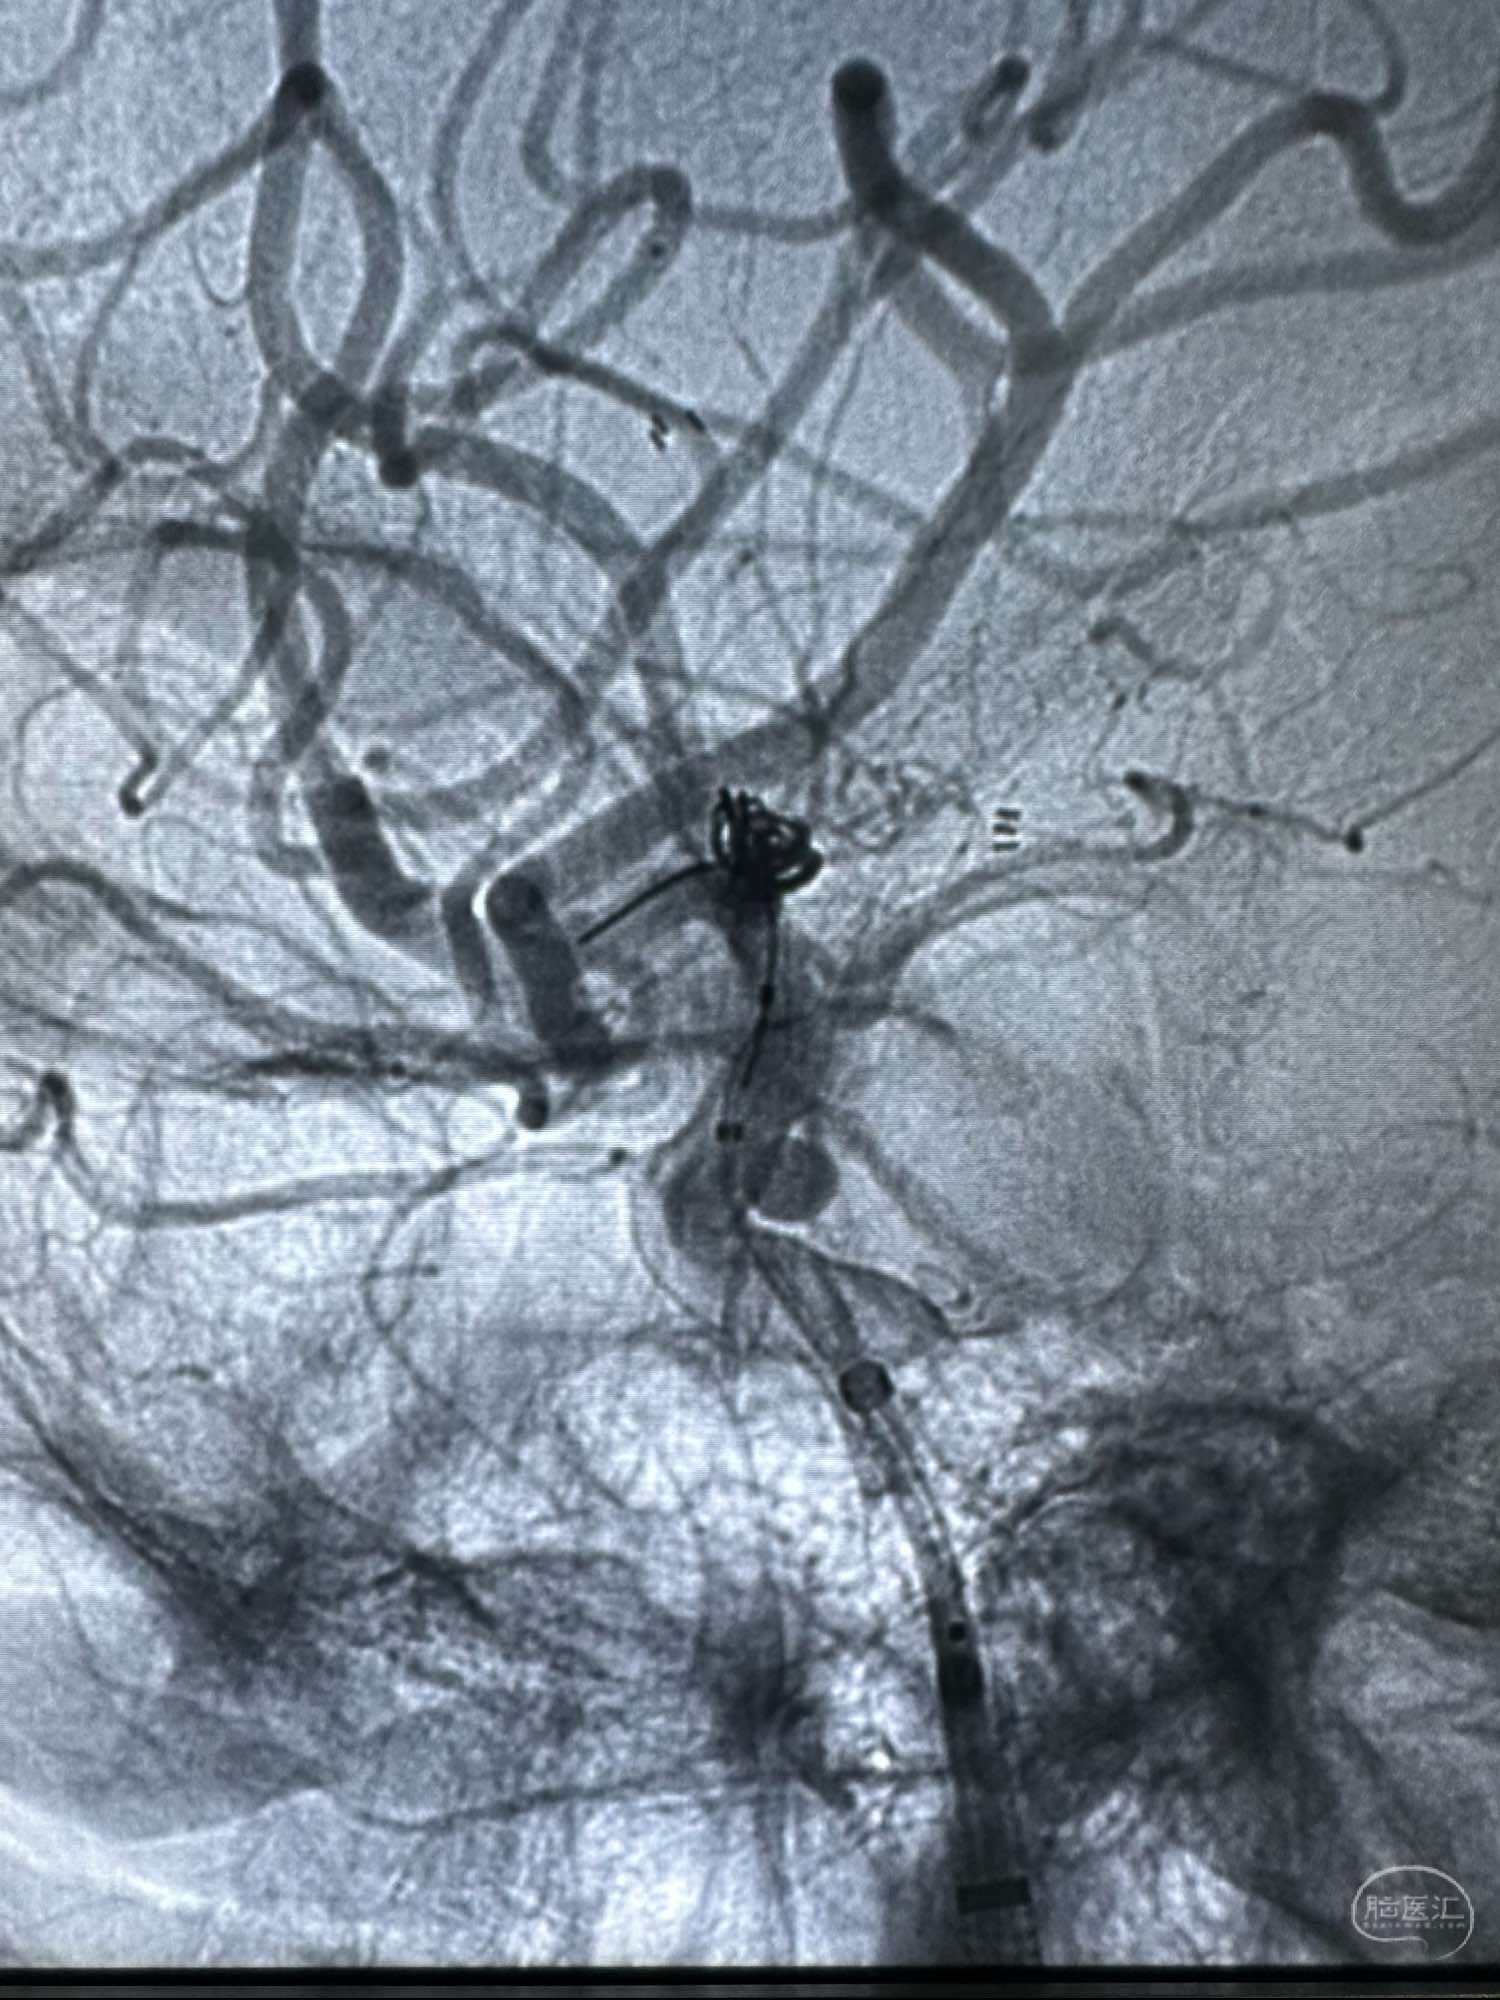

原味释放

支架的头段打开不良

给予推拉技术处理

支架打开后形态

给予导丝按摩

支架有所移位,不过还好,头段还能覆盖

原味释放

支架的头段打开不良

给予推拉技术处理

支架打开后形态

给予导丝按摩

支架有所移位,不过还好,头段还能覆盖